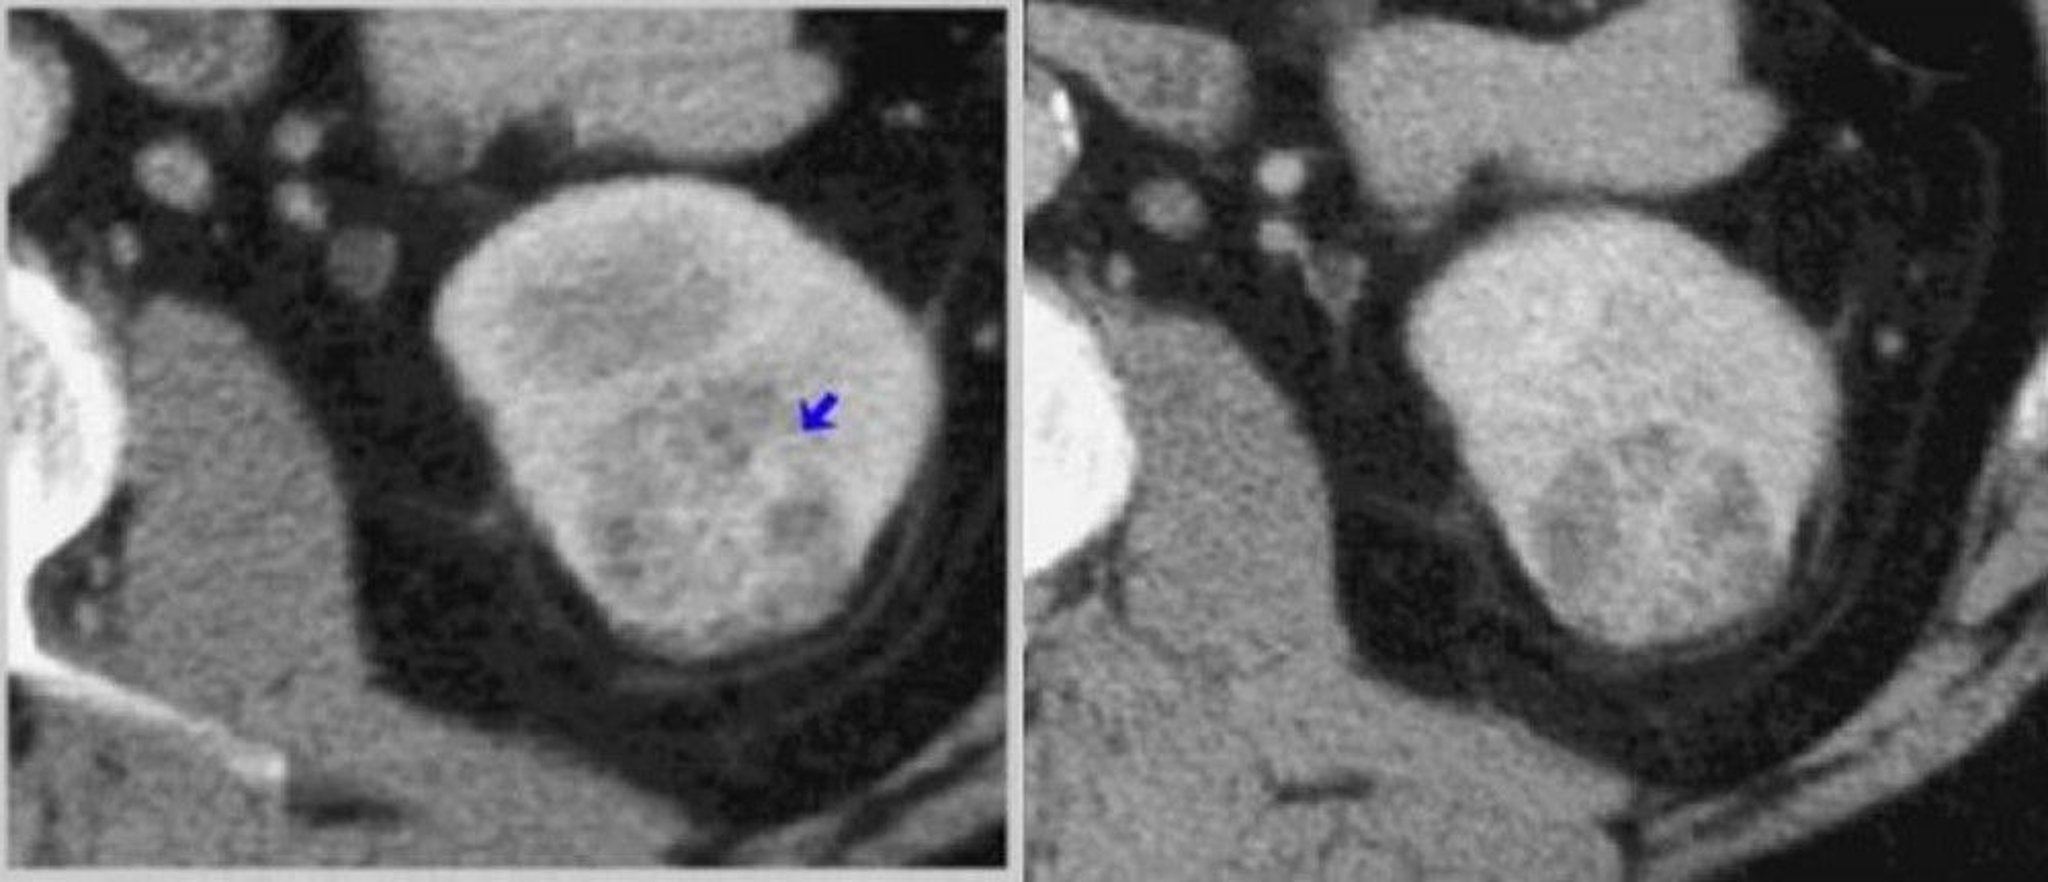

Contrast CT Scan of the Kidney (Corticomedullary and Nephrogenic Phases)

On the left, a corticomedullary phase CT scan shows a heterogeneously enhancing tumor (arrow). On the right, a nephrographic phase CT scan better defines the tumor.